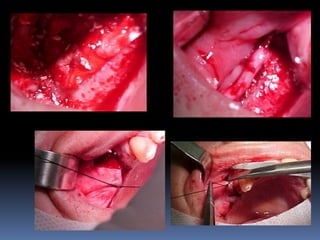

Atrofias ósseas

•Procedimentos de enxertia óssea para

restabelecimento de dimensões perdidas

•Compensações dos tecidos perdidos nas

próteses